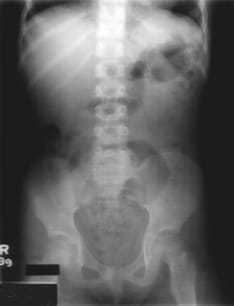

A 6-year-old boy presents with a 3-month history of soiling his underwear almost daily, despite being toilet trained at 2 years of age without difficulty. He has also experienced ongoing constipation for the last 2 years and frequently states, "I didn't know I had to go." He is otherwise healthy, performing well in school, and has a stable home environment. Examination reveals stool in the rectal vault. A plain radiograph of his abdomen is provided. What is the most appropriate initial management for this condition?

Explanation: ***Disimpaction and short-term use of stool softeners*** - This is **functional encopresis with overflow incontinence** secondary to chronic constipation, requiring immediate **disimpaction** to remove the fecal impaction in the rectal vault. - **Stool softeners** (like polyethylene glycol) help maintain soft stools and prevent re-impaction while establishing regular bowel habits. *Barium enema and rectal biopsy* - These investigations are indicated for **Hirschsprung disease**, but this child was toilet trained normally at age 2, making congenital causes unlikely. - The history of **successful toilet training** and **gradual onset** of symptoms suggests functional rather than anatomical causes. *Family counseling* - While supportive care is important, **medical management** must address the underlying fecal impaction first before behavioral interventions. - Counseling alone cannot resolve the **physical obstruction** causing overflow incontinence and loss of rectal sensation. *Time-out when he soils his underwear* - **Punitive measures** are contraindicated as the child has **lost rectal sensation** due to chronic distension and cannot control the soiling. - Such approaches can worsen the condition by increasing **anxiety** and **shame** around bowel movements, perpetuating the cycle of withholding.